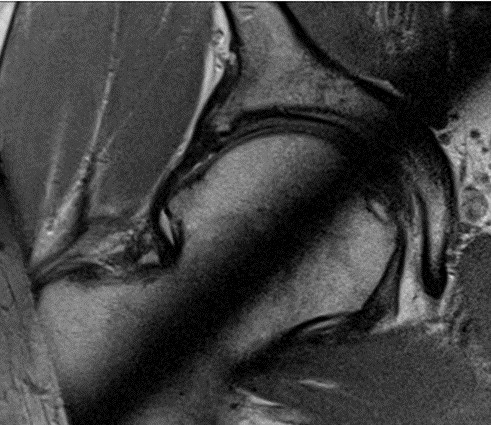

Badaniem obrazowym pokazującym najlepiej szczegóły stawu ramiennego takie jak stan obrąbka, uszkodzenia kostne, stan pierścienia rotatorów jest: